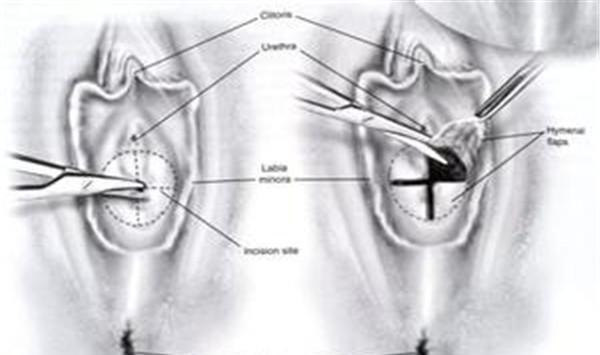

石女分为“外石”和“内石”,“外石”也称“假石”,是指由于处女膜肥厚或闭锁,无法顺利进行性生活,这种情况进行处女膜切开手术即可治疗,术后能过正常的性生活;

图片来源:网络搜索

有无阴道的女性却有发育正常的子宫,可以产生月经,但无法排出去,形成与处女膜闭锁相似的症状,该类情况应在初潮年龄进行手术。如果经血不能顺利排出,血液在阴道内集聚,流到子宫,积血过多可流入输卵管,通过伞部进入腹腔,伞部附近的腹膜受经血刺激发生水肿,长期以往,可能会诱发炎症,造成骨盆组织粘连、感染等。

总而言之言而总之,无论是哪种情况,在初潮到来之前,很少有人能够注意到这一问题,大多是青春期后长期未来月经或性行为无法进行时才被发现。所以,新生儿的生殖系统检查也就尤为重要。不过现如今,大多数“石女”可以通过外科手术来治疗,较于相对严重的先天性,治疗方法也日渐成熟。